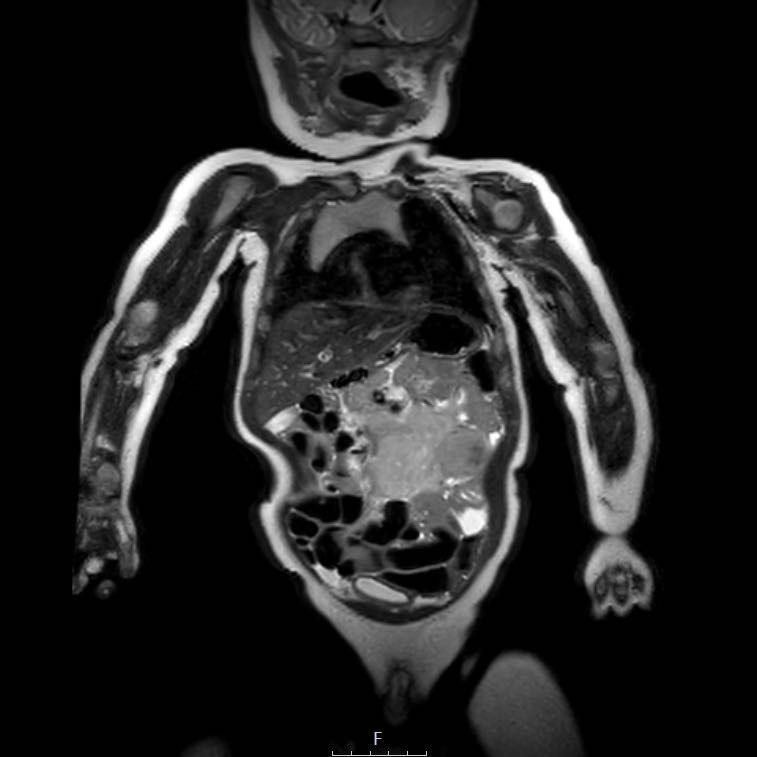

Ví dụ 1

Hình ảnh của một bé trai hai tuổi, đến khám với triệu chứng bụng phình to không đau. Siêu âm cho thấy một khối đa nang lớn ở phía đuôi của gan.

Continue with the MRI.

MRI tương phản T1 có ức chế mỡ mặt phẳng coronal cung cấp cái nhìn tổng quan tốt hơn về tổn thương gan, với trọng lượng gần 2 kilogram khi cắt bỏ.

Kết quả giải phẫu bệnh cho thấy u hamartoma trung mô. Không cần theo dõi thêm.